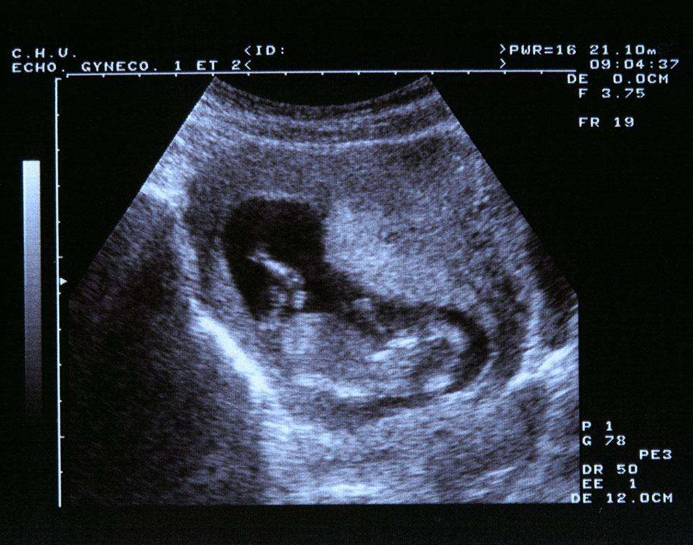

甲狀腺素是胎兒腦神經、生長發育等重要激素,而胎兒20周之前,是第一個腦快速發育階段;胎兒生長發育需要的甲狀腺激素全靠母體,因為胎兒12周才開始分泌,20周以后甲狀腺功能才建立。所以,孕媽健康,才能保證胎寶寶腦快速發育期的甲狀腺需求。

在孕期的每個階段,母體的甲狀腺激素都不能少,即使是輕微的,也會影響到胎寶寶的腦部發育,且損害是不可逆的,孩子出生后表現智力低下、身材矮小,即呆小癥。